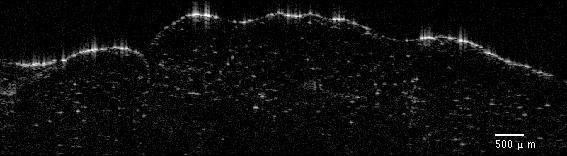

Typical OCT images of normal and tumor tissue types are shown in Figure 2. The OCT image was cropped to 1.5 mm (horizontal) ×\times 0.75 mm (axial) to show the tissue part of the image. A clear structural difference can be observed between the adipose tissue and the tumorous tissue: As the adipose tissue is composed of relatively large cells, a kind of periodicity is observed in the related images. The images of timorous tissue have less clear spatial structure.

(a) OCT image of adipose tissue

(b) OCT image of tumorous tissue

Figure 2: Breast OCT images.